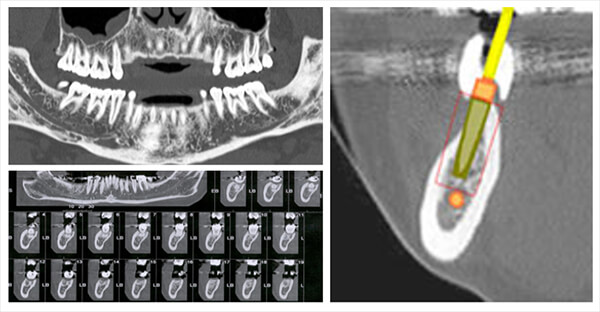

Mandible

It allows the visualization of the mandibular canal as well as the visualization of the pre implanted bony space.

Bronchial Tree

This image shows us the visualization of the bronchial lumen and its caliber.